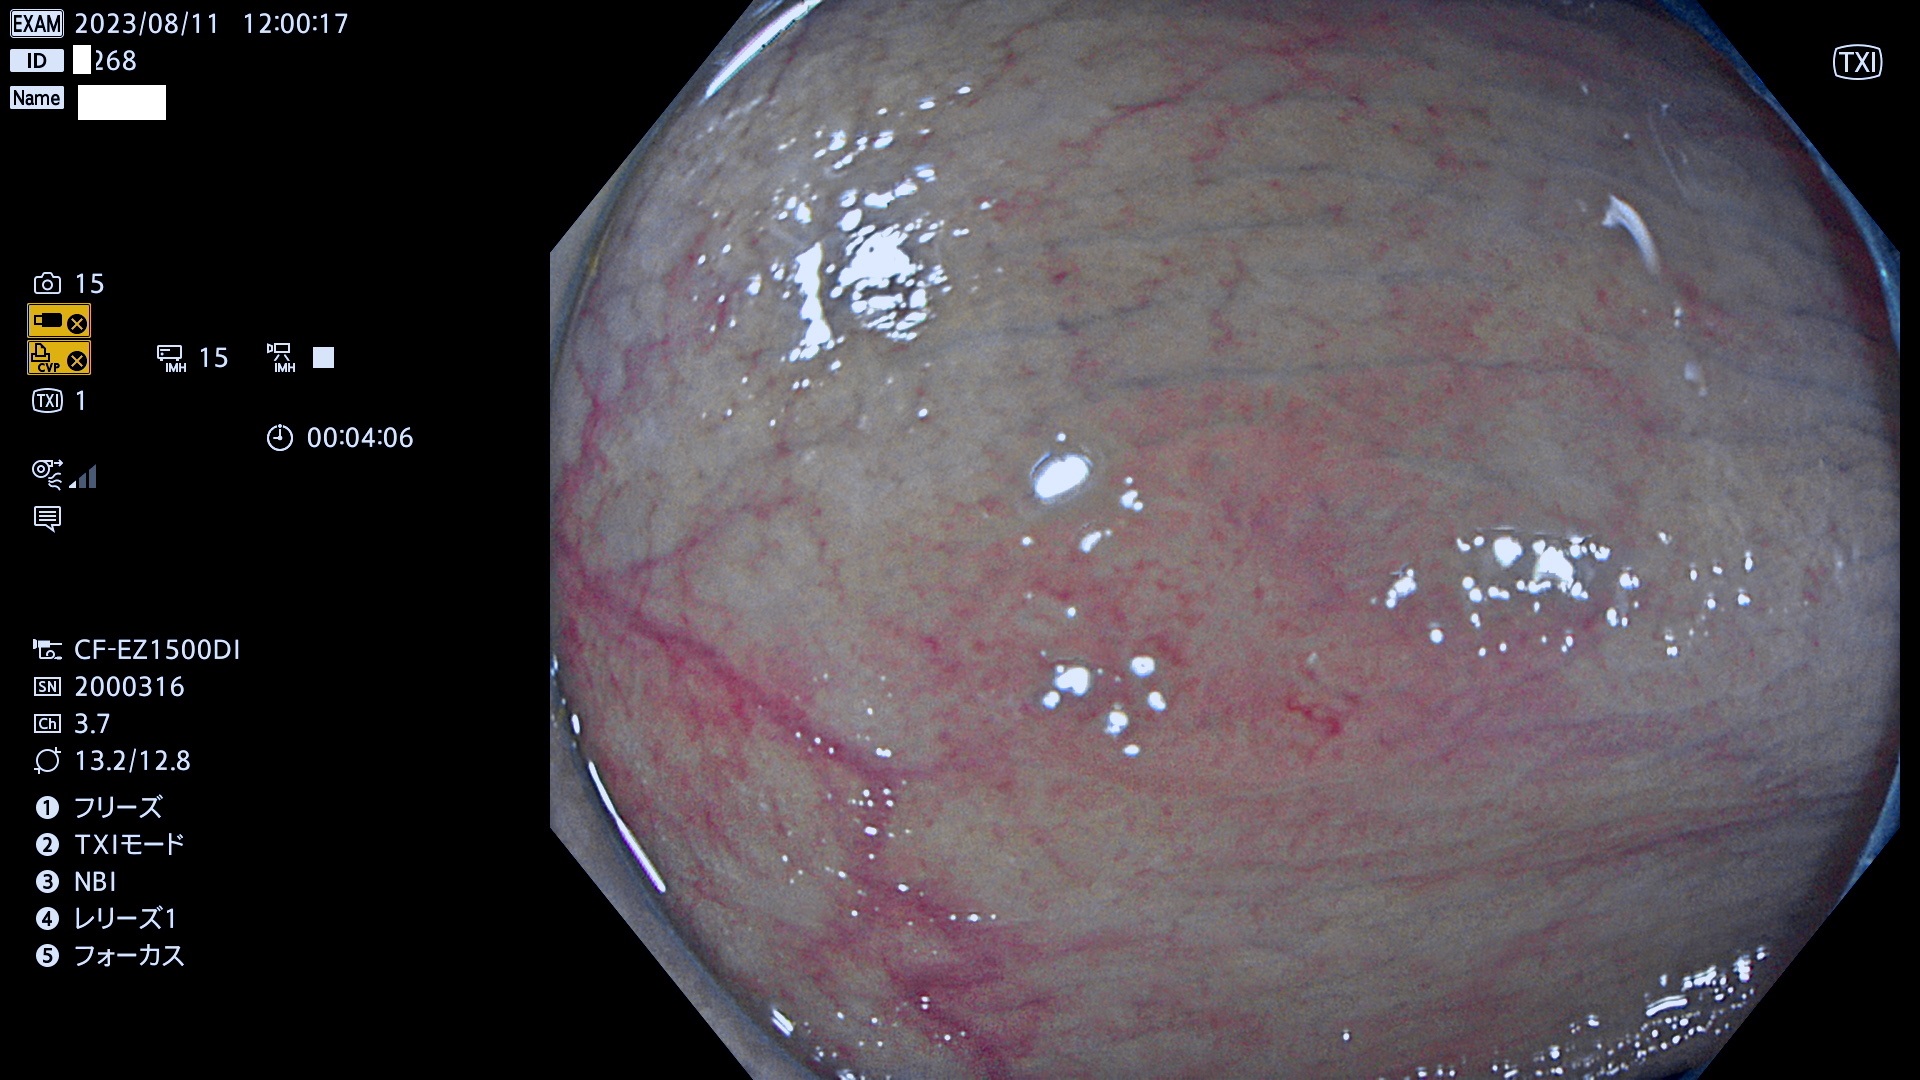

今週のUb、Uc型腺腫

表面型腺腫(Flat Adenoma)の中で、完全に平坦な物をUb、陥凹している物をUcと呼びます。平坦隆起型(Ua)よりも、発見が難しく危険な病変です。このタイプは「内視鏡後・大腸癌の重要犯人」であり、この発見率は「腺腫発見率」よりも、重要な意味があります。

毎週の検査(木・金・土・日)に発見されたUb、Uc型・腺腫を、その週の日曜の夜にUPし1週間、提示します。

抽出の対象期間 2023年8月10日(木)〜8月13(日)の4日間(48件の検査)11件